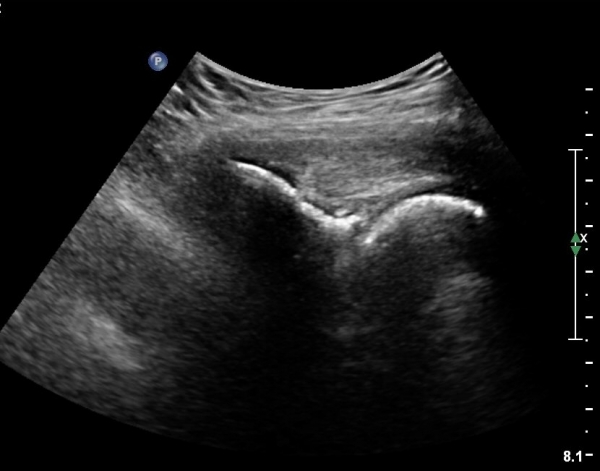

ÃÊÀ½ÆÄ °Ë»ç